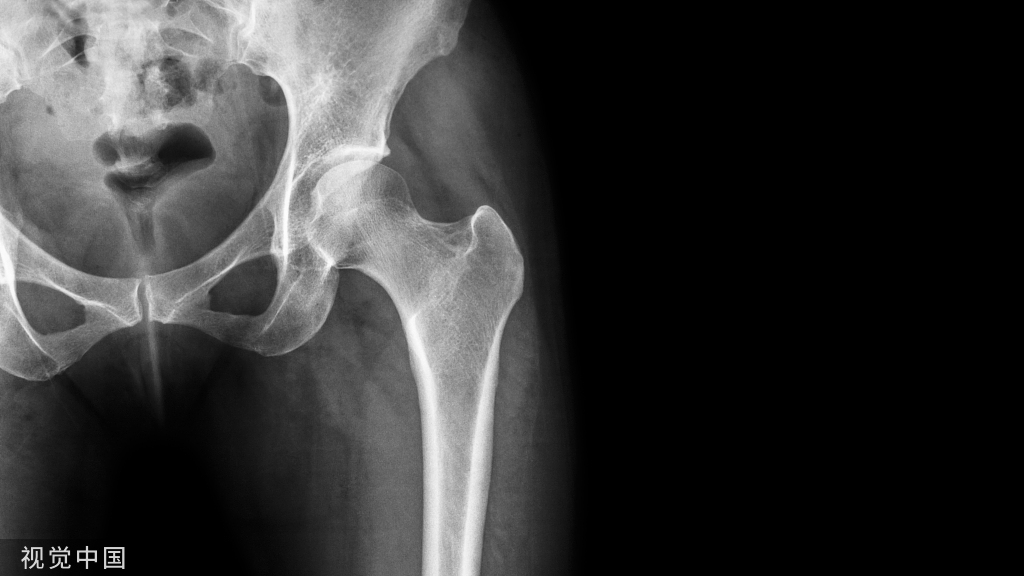

是脊神经根离开脊髓通过的孔道,其上下壁是椎弓根的切迹;前方为椎体外侧缘、椎间盘和后纵韧带;后方为小关节的关节囊及部分黄韧带。神经通过椎间孔的管道中,被一些蜂窝组织和小血管所包绕。神经根自离开硬膜囊到出椎间孔的一段路程的总称为“神经根管”。它的外侧份为椎间孔,内侧份为侧隐窝。侧隐窝的前壁是椎体和纤维环的后外侧,外壁为弓根内侧面,内侧为硬膜外脂肪及马尾神经囊,后壁为上关节突和黄韧带的侧份。侧隐窝向外下续为椎间孔。椎管狭窄一般分为先天(原发)、后天(继发)两种因素所造成,实际上这两种因素是相互联系、相互影响的。胎生时腰椎椎管呈卵圆形.但随着人体的发育、负重、退行性变和各种超负荷的增加,则促使其向增加力学强度的方向发展。至成年时腰;至骶。和腰4~5大多呈三角形或三叶草形并使腰骶关节承受60%~75%的伸屈活动量。腰。、腰。为15%~20%。此种椎管虽然力学程度增加,但矢状径减少。加之小关节部骨质增生、肥大,.或上关节突过长以及椎体间关节的退行性变,不仅椎管矢状径变短,容积明显减少而且神经根管也相应地细而短。由于管内有效容积的缩小,致使马尾与神经根处于临界状态。任何可以增加管内压力的病理与生理因素,如骨刺、关节囊和黄韧带的松弛与肥厚、椎板、关节突增生肥大.纤维环的膨出等退行性变.增加了狭窄程度,直接压迫或刺激马尾和脊神经根引起腰椎管狭窄症。根据椎管狭窄部位与程度分中央型、侧隐窝型(根型)和混合型。中央型椎管狭窄多见先天软骨发育不良和退行性变。椎管的前后径与宽度均狭小,椎管矢状径小于10~12mm。主要表现为马尾神经源性间歇跛行。侧隐窝狭窄(根管)和椎间孔狭窄多为椎体后外缘骨赘增生或关节突增生肥大,侧隐窝的矢状径小于4mm;椎间孔可行两侧比较判定它有无狭窄。主要表现为根性神经痛。混合型椎管狭窄,即上述两种类型中两种因素的混合,既有间歇性跛行又有根性神经痛。

侧隐窝位于侧椎管。其前面为椎体后缘,后面为上关节突前面与椎板和椎弓根连结处,外面为椎弓根的内面。内侧入口相当于上关节突前缘。侧隐窝为椎体孔两侧向外陷入部分,向外下方形成脊神经根通道,与椎间孔相续。侧隐窝是椎管最狭窄部分,为神经根的通道,其矢径越小,横径越大,表示侧隐窝越窄越深。侧隐窝狭窄卡压神经根是腰腿痛的原因之一。腰5椎间孔最易引起侧隐窝狭窄,原因是:①椎间孔多呈三叶形;②侧隐窝明显,矢径可小至2~3mm;③上关节突增生变形较多。